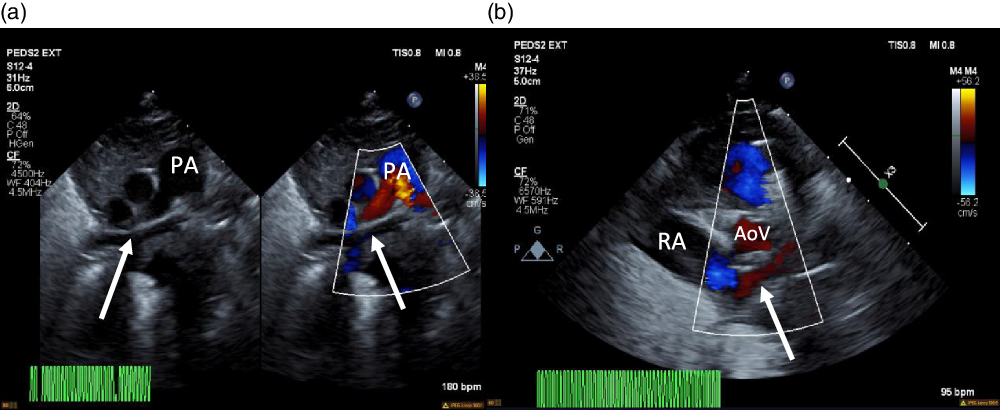

On arrival, the patient remained on an alprostadil infusion at 0.1 mcg/kg/minute, with oxygen saturations persistently in the 50’s despite ongoing respiratory support with nasal continuous positive airway pressure with FiO2 100%. The patient was immediately intubated but remained significantly desaturated. Repeat echocardiogram was obtained (Fig 1), which revealed the absence of pulmonary veins entering the atrium and absence of dilated pulmonary veins or large vertical vein. There was all right to left shunting across an unrestrictive atrial communication, and there was a large patent ductus arteriosus with predominantly right to left flow. A trivial pulmonary vein confluence was seen posterior to the left atrium. The right ventricle was dilated and the left ventricle was apex forming but appeared underfilled. Given that discrete pulmonary veins or venous drainage could not be delineated by echocardiography, cardiac CT scan was emergently obtained. Cardiac CT revealed a trivial pulmonary venous confluence with small left and right veins posterior to the left atrium; however, no discrete connection to the heart was identified (Fig 2). Due to the near atretic nature of this patient’s pulmonary veins and common pulmonary vein and lack of identified collaterals, extensive multidisciplinary discussions were held between Cardiology, Cardiac Intensive Care, Radiology, and Cardiothoracic Surgery teams. Ultimately, it was determined that there was no viable operative repair, and the decision was made between the family and the medical team to proceed with withdrawal of care. The patient was transferred back to the cardiothoracic ICU, compassionately extubated, and died shortly thereafter. An autopsy was performed which confirmed the absence of any pulmonary venous connection to the left atrium. There was a trivial pulmonary venous confluence superior to the left atrium as noted on the echocardiogram and CT, with a trivial vein that appeared to drain from the confluence to the innominate vein. No dilated pulmonary veins were demonstrated by autopsy. On gross examination, the lungs had a diffusely nodular appearance and histological examination revealed findings consistent with cystic lymphangiectasia.

Figure 1. ( a ) 2D echocardiogram and colour echocardiography. Seen (arrows) is a trivial pulmonary venous confluence coursing superior to the left atrium (not seen). ( b ) Colour echocardiography. Underfilled left atrium (arrow) seen demonstrating the absence of pulmonary venous return to the left atrium; notably the right atrium is dilated. AoV = aortic valve; PA = pulmonary artery; RA = right atrium.